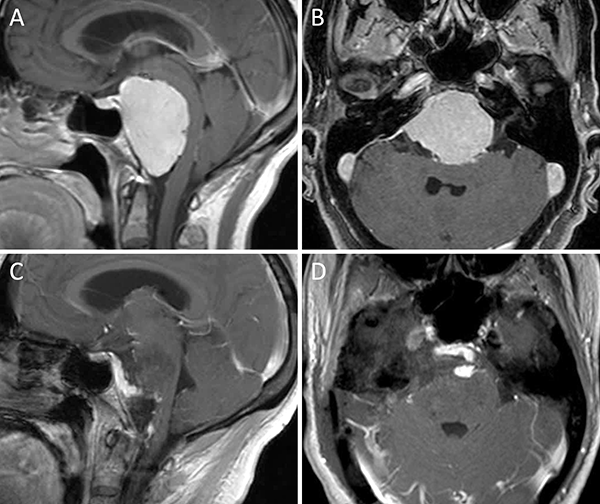

Figura 3. Meningioma clival. A-B: RM preoperatoria; C-D: RM postoperatoria.